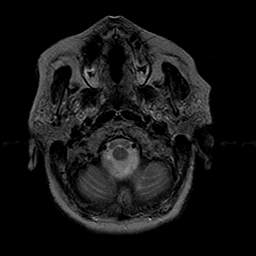

Stroke:T2-weighted MR #1 -- Slice #1

[Home][Help][Clinical] Slice 1